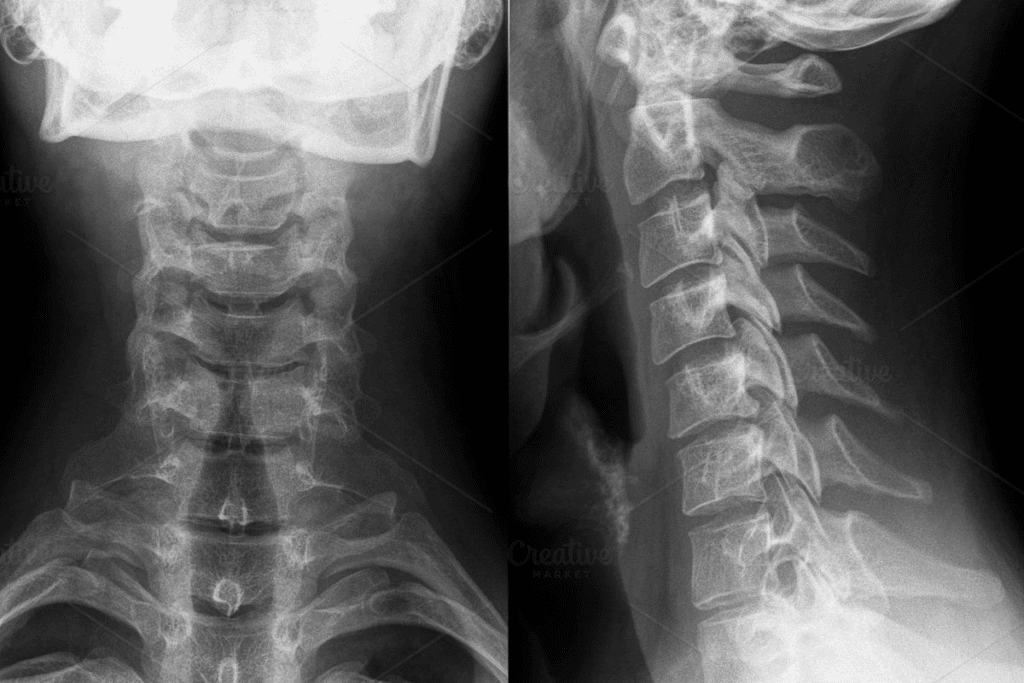

Cervical (Neck) Facet Injections

Cervical facet injections help with neck pain. They treat the facet joints in the neck. This is for pain caused by injury, wear and tear, or other reasons.

To do these injections, we use special X-ray guidance. This is key in the neck because of its complex anatomy.